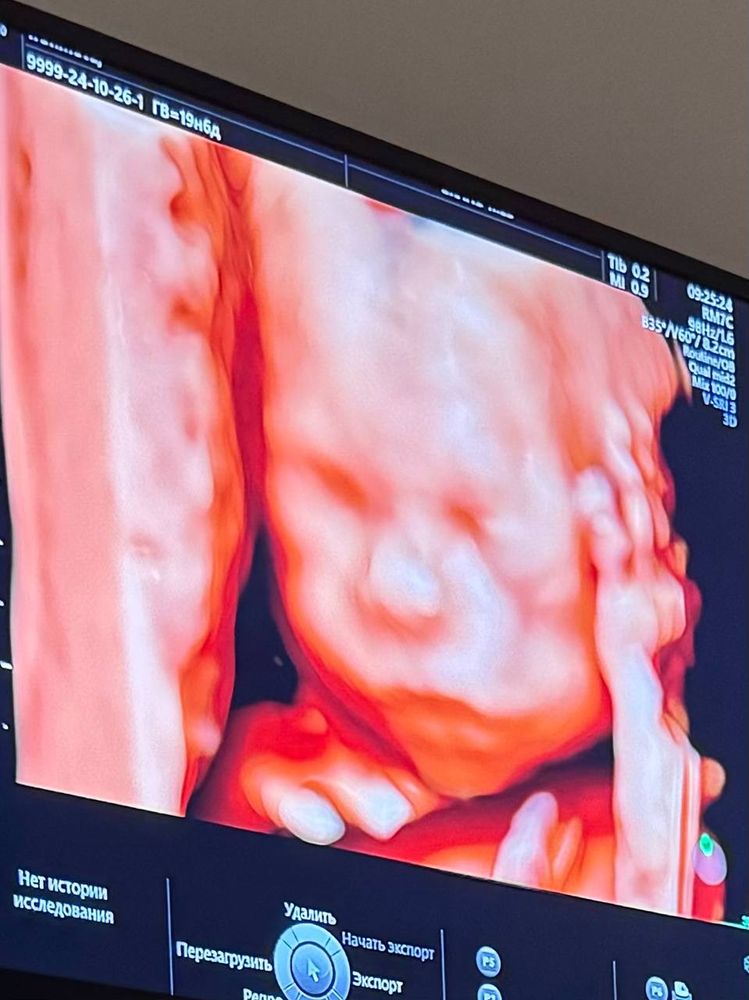

19 недель + 6 дней. Скрининг второго триместра

Всё хорошо, замеры соответствуют сроку беременности. 340 грамм) Аномалий не обнаружено. В связи с обнаруженной повышенной толщиной воротникового пространства на 1 скрининге рекомендовано дополнительное УЗИ между 2 и 3 скринингом. Ничего страшного не ждем, на всякий случай еще раз посмотреть как развивается мозг